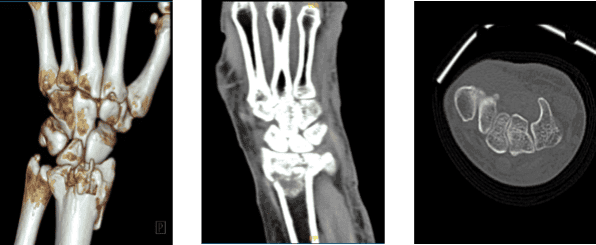

The patient presented today is 68-year-old, female and having a complaint of her left hand and wrist after getting injured because of a fall. Her Xray result showed a fracture but we wanted to make sure of the diagnosis. We agreed to take CT-Scan.